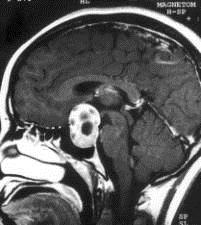

问题 病历摘要:??患者男性,35岁。性功能减退2年,视力下降6月。既往体健。体检:神清,皮肤细腻,毛发稀疏。视力左眼0.3,右眼0.5,双瞳等大等圆,直径3.5mm,对光反射稍迟钝,双颞侧偏盲,双眼底视神经乳头原发性萎缩,余神经系统未见异常。 入院后应申请哪些辅助检查?

选项 A.内分泌功能检查 B.脑电图 C.头颅平片 D.头颅MR E.TCD F.SPECT G.CT H.PET

答案 ACDG